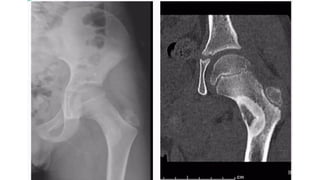

• A lucent lesion typically situated beneath the articular surface

• E c c e n t r i c

• Narrow z o n e o f transition

• 'soap-bubble' pattern of calcification

• No sclerotic margin

• • overlying cortex is thinned, expanded or deficient

• • Soft-tissue mass may be present

• • No calcification or ossification until complicated by f r a c t u r e

Plain film & CT features